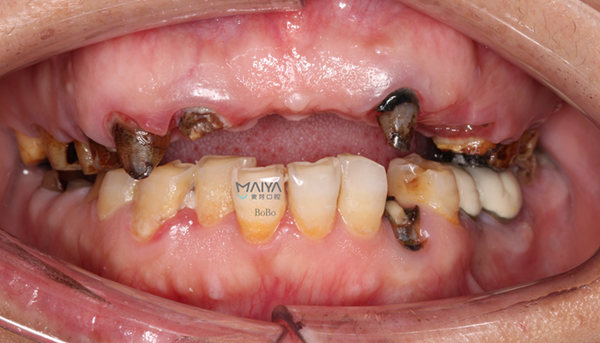

10年前因为无法忍受自己发黄、畸形、排列不齐的牙齿,我把上颌包括门牙在内的牙齿全换成了烤瓷冠。但由于当时选择的材料和医生技术不过关,做的烤瓷冠密闭性不好,导致牙齿里面的牙根慢慢发炎、腐烂、松动。不仅无法尽享美食,而且形象也受影响。

郄女士牙齿情况

我希望修复后的牙齿不仅要美观,还要能好用,麦芽种植专家反复对治疗方案进行设计修改,最终决定采取"麦芽即刻种植即刻修复技术",并对上颌前牙区牙槽骨进行修整术,满足了我对外观和功能的双重需求。